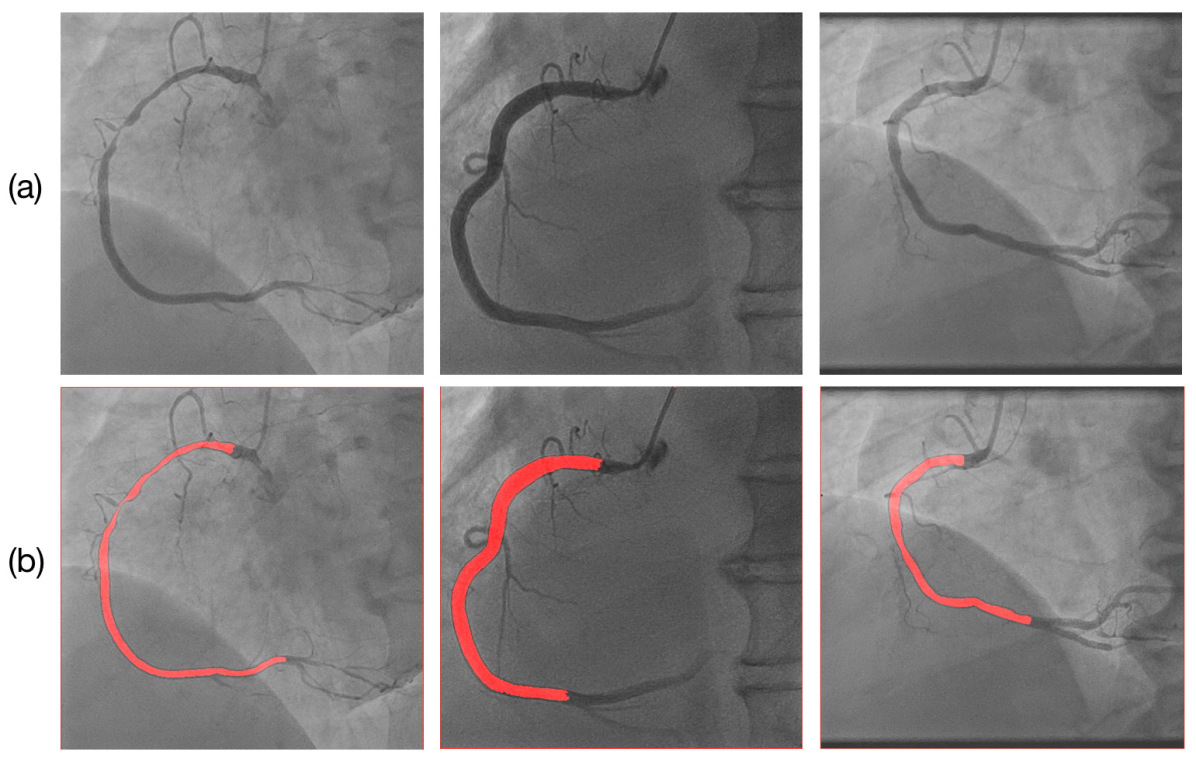

Figure 3: Illustration of LAO and RAO results. (A) Temporal score variation over the course of an LAO angiography video. Each data point represents the machine predicted score of that frame. Three particular frames are highlighted in red as they represent the frame just before, in and after the “key frame region”. (B) Machine’s inferential ability shown by noisy incorrect LAO labels detected by the model. First image: a key frame erroneously labeled as non-key in manual labeling, and the model gave the frame a high score (0.998) Second image: a non-key frame with vessel shifted out erroneously labeled as a key frame; it was detected and given a low score (0.083) (C) LAO vessel segmentation, (a) original images, (b) segmentation masks. (D) RAO vessel segmentation, (a) original images, (b) segmentation masks. (E) Erroneous LAO segmentation near the RCA bifurcation point. (F) Identification of LAO stenosis location and estimation of severity. (G) Side-by-side comparisons between LAO and RAO stenosis measurement. Each column represents one patient.

where predictionprediction\operatorname{prediction} and truelabeltruelabel\operatorname{truelabel} are arrays representing generated and ground-truth masks respectively. Our segmentation model can localize heart vessels with relatively high precision (Fig. 3C). Comparing the performance of our model with Yang et al. [19], our model using a similar but much smaller training dataset (102 vs 1021 patients) was able to reach a comparable result (Table. III). Our neural network architecture was also of lower complexity, requiring less computational power for training, albeit prone to errors especially near the distal RCA bifurcation (Fig. 3E). More complex U-Net architectures and more training data will improve the performance in these difficult areas.